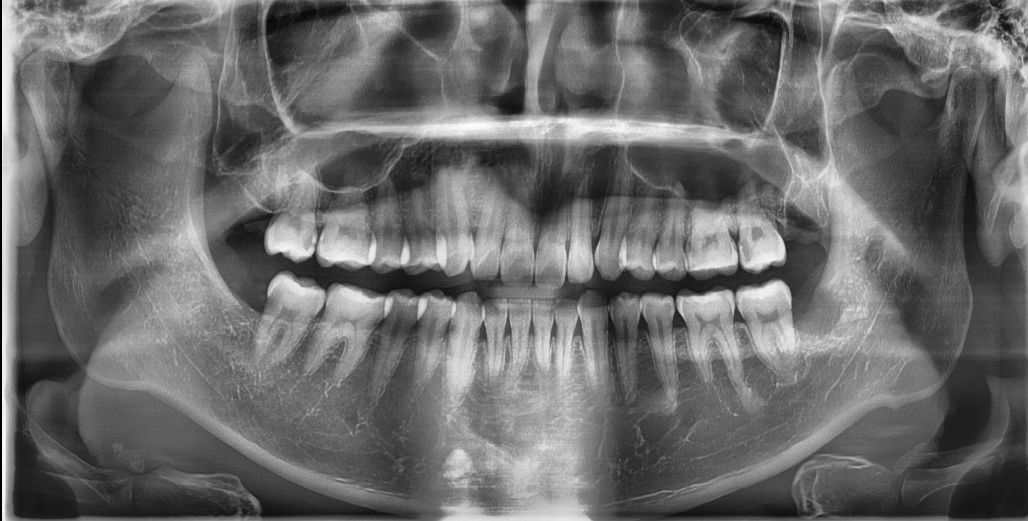

오른쪽 아래 어금니 치료 여부 질문입니다.

오른쪽 아래 어금니가 전에 발치했던 매복 사랑니 때문에 충치가 생겼고 깊다고 합니다.

방문 했던 다섯 치과 중 네 곳은 크라운 치료 및 신경치료까지 갈 수 있다고 하는데

한 치과는 사랑니 발치 후 잇몸이 어금니 충치를 덮었기 때문에 충치가 더 이상 진행이 안될 것 같아서 지금은 치료가 필요 없다고 하는데 어떤 치과에서 치료를 받아야 할까요?

• 1번 째 사진

1. 증상이 없으니 지켜보자. 썩어 잇는 부분은 굉장히 안좋은 부위에 충치가 잇습니다. 증상이 나타나면 발치를 해야될 가능성도 잇습니다

2. 증상이 없으니 신경치료해서 살려보자 하지만 발치 가능성은 잇습니다.

저라면 신경치료를 해서 크라운치료를 할것같습니다.